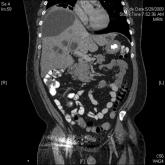

A Multiple Choice Answer?